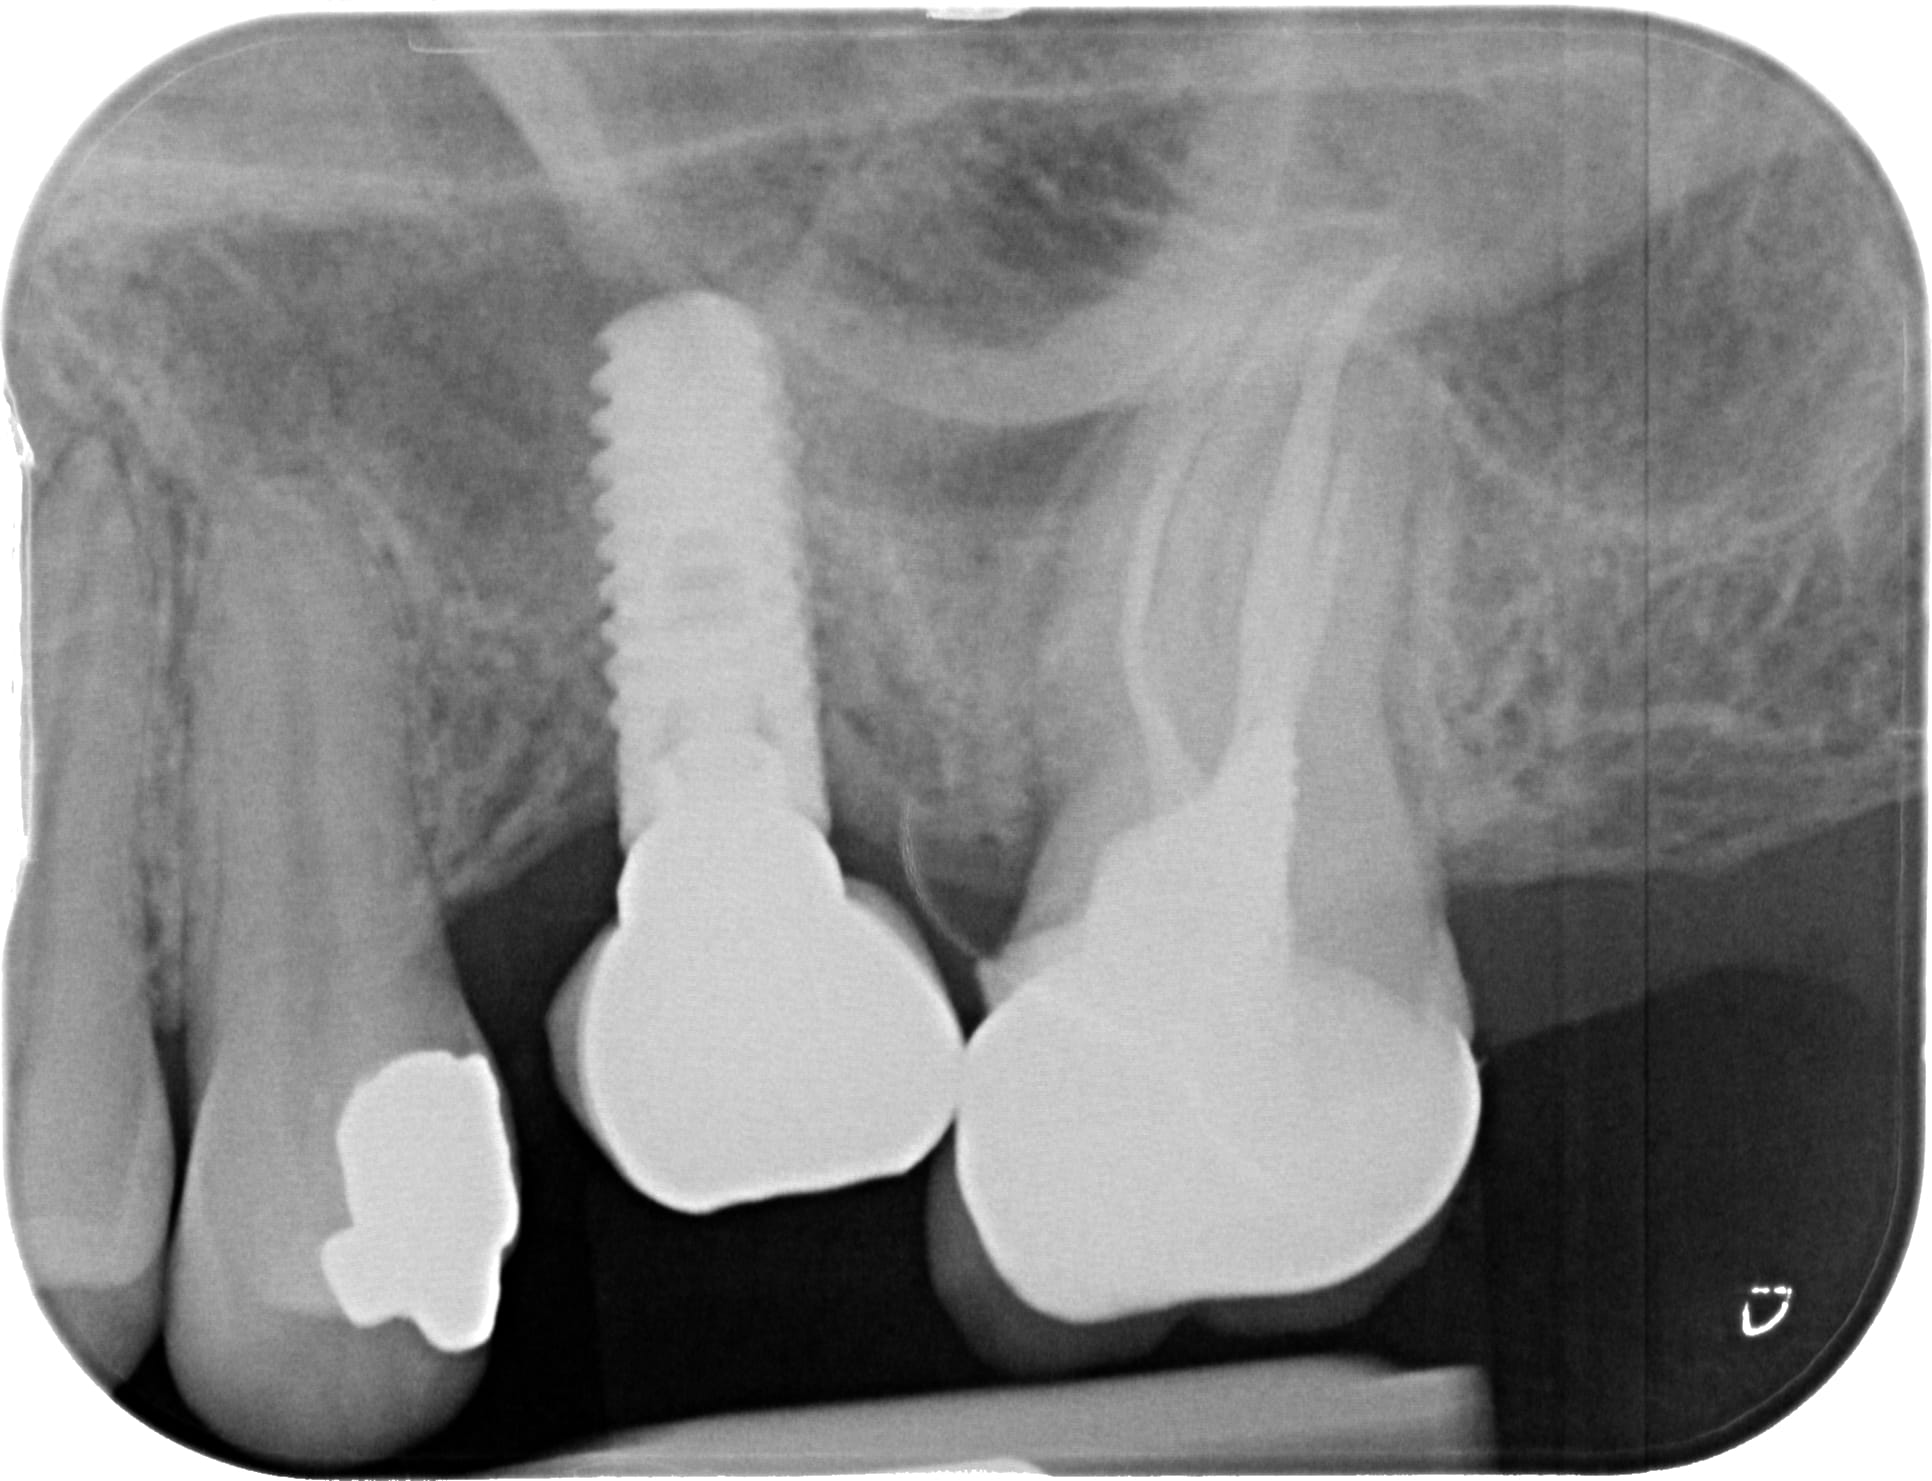

oui désolé... c'est mieux? plutôt Nobel la 35 non ?

les 2 autres photos (du même implant)....çà ressemble à du MIS Lance ou similaire....pour moi la connexion doit être un standard "Zimmer"....